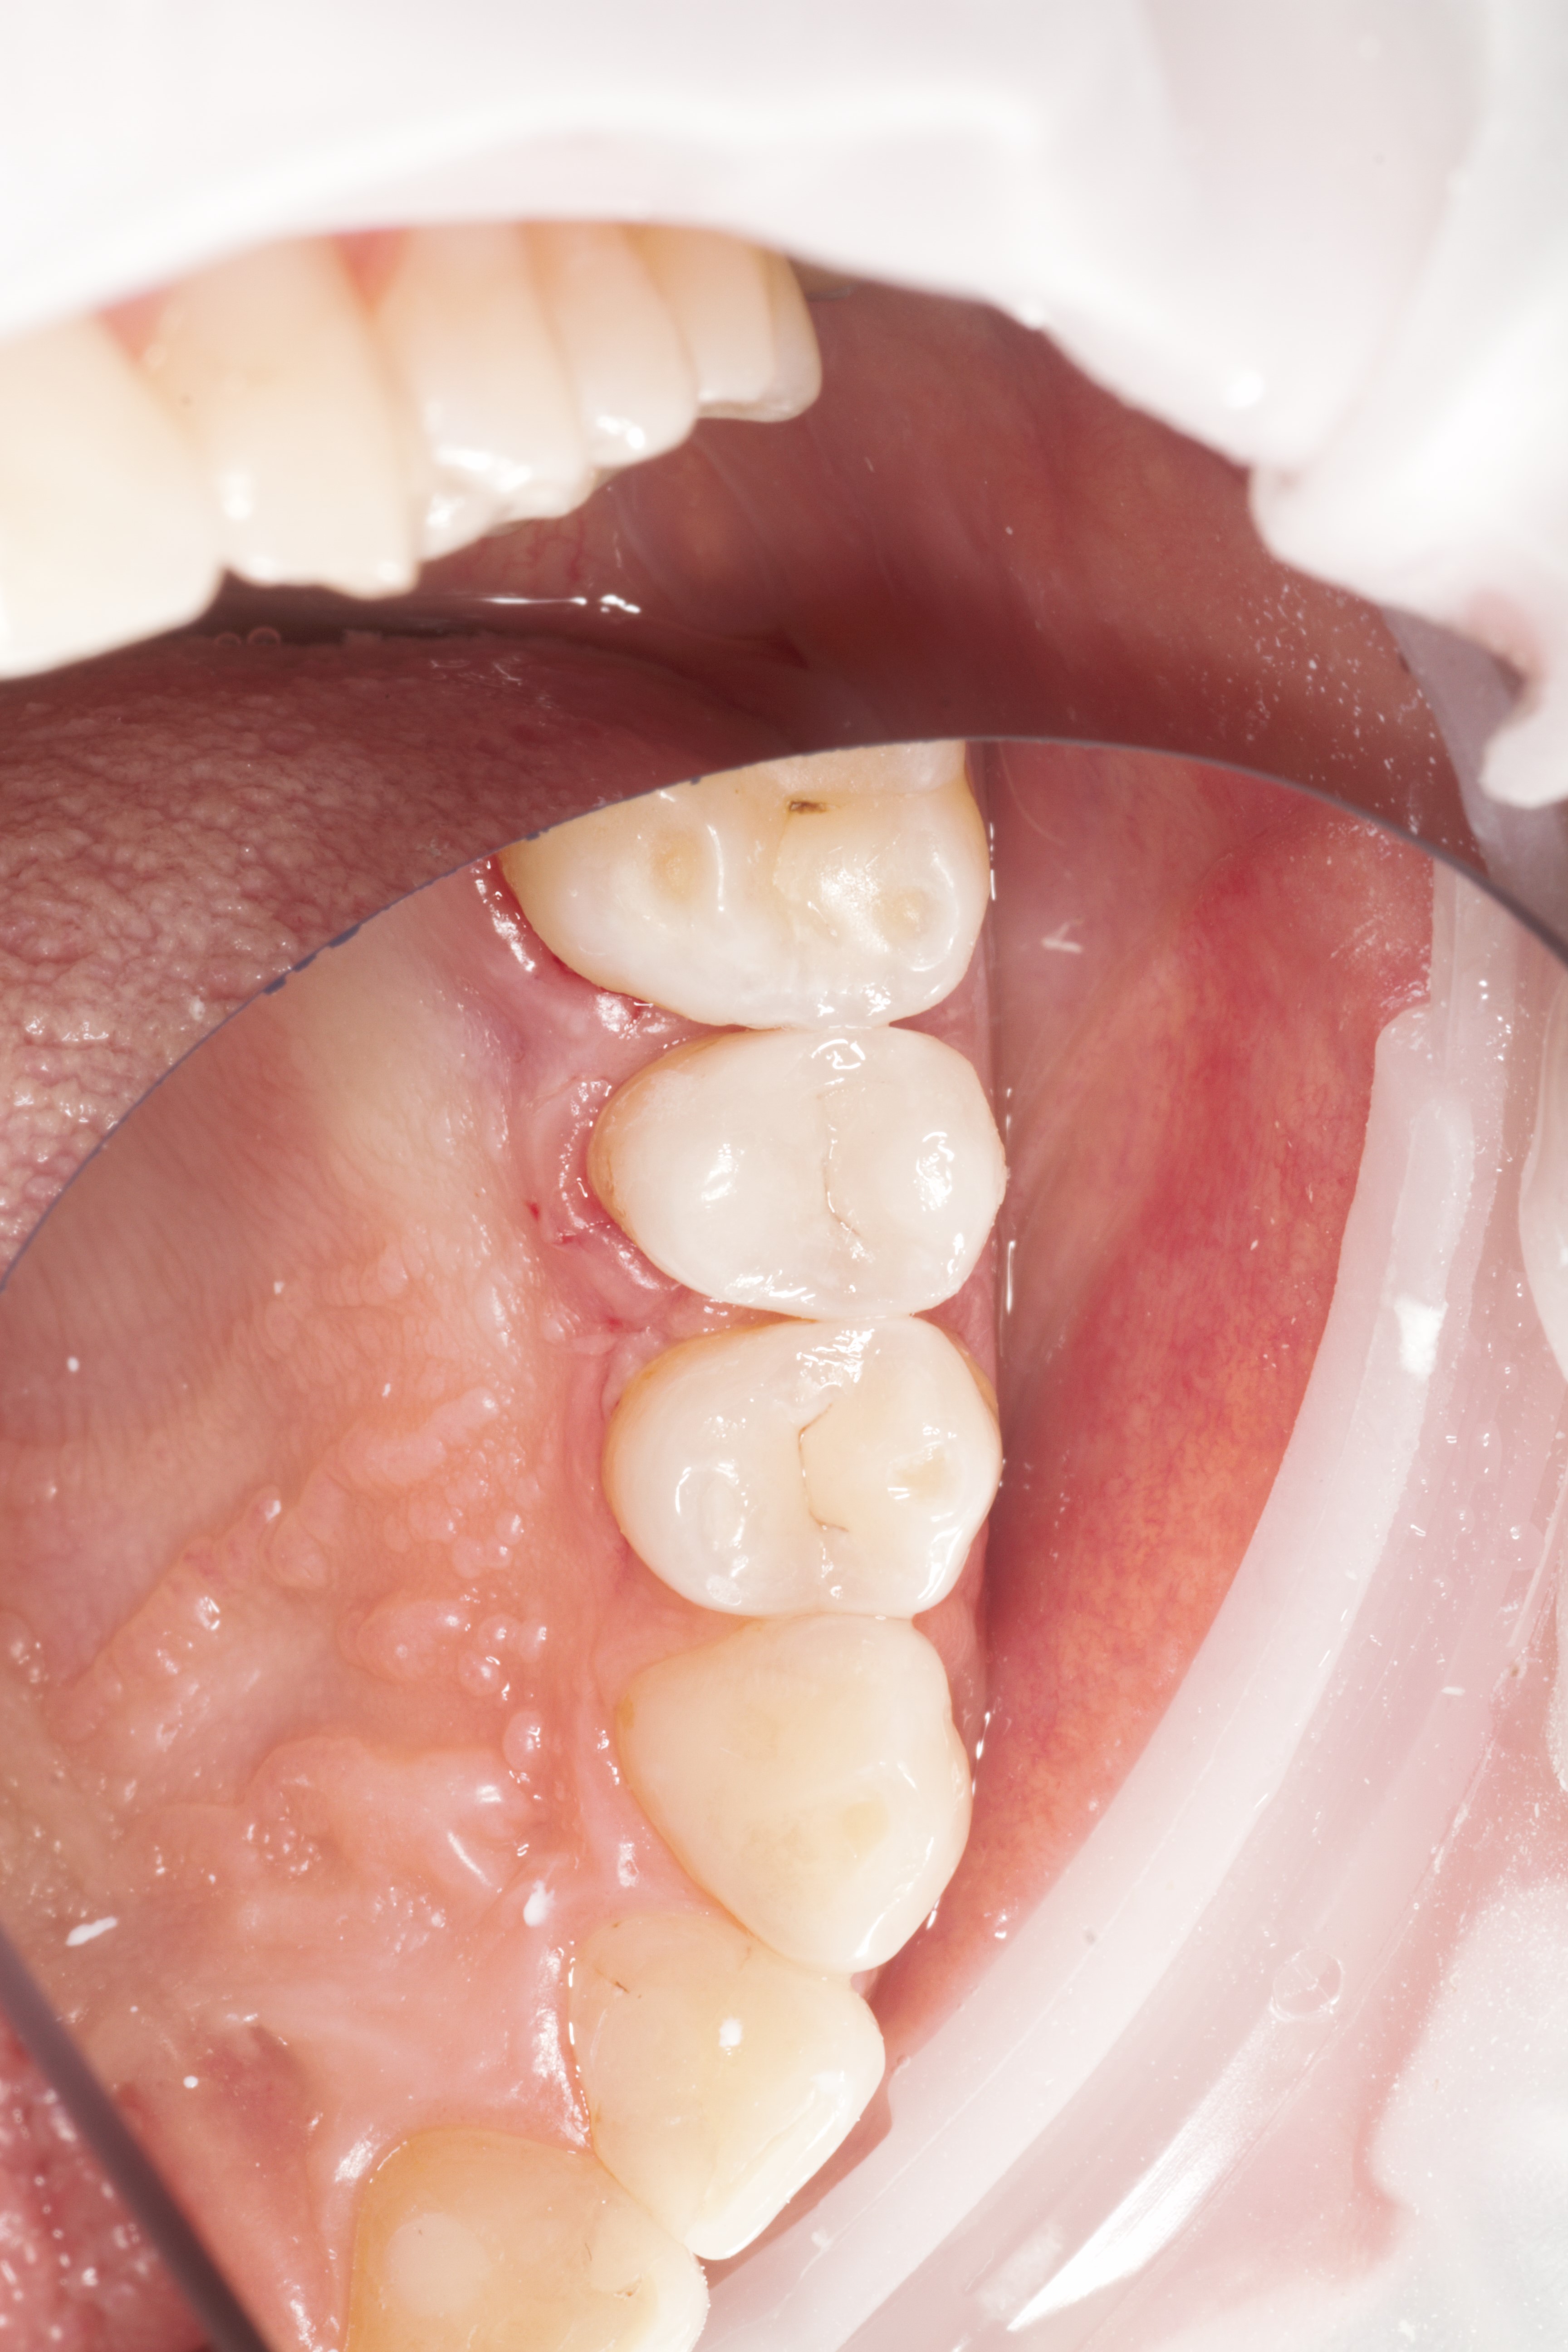

- Эстетическая реставрации жевательной и фронтальной группы зубов современными пломбировочными материалами, диагностика кариеса на ранних этапах развития, предупреждение образования вторичного кариеса в области запломбированных зубов

- Владение современными методиками пломбирования корневых каналов, обработки и распломбировки многокорневых зубов любой степени сложности